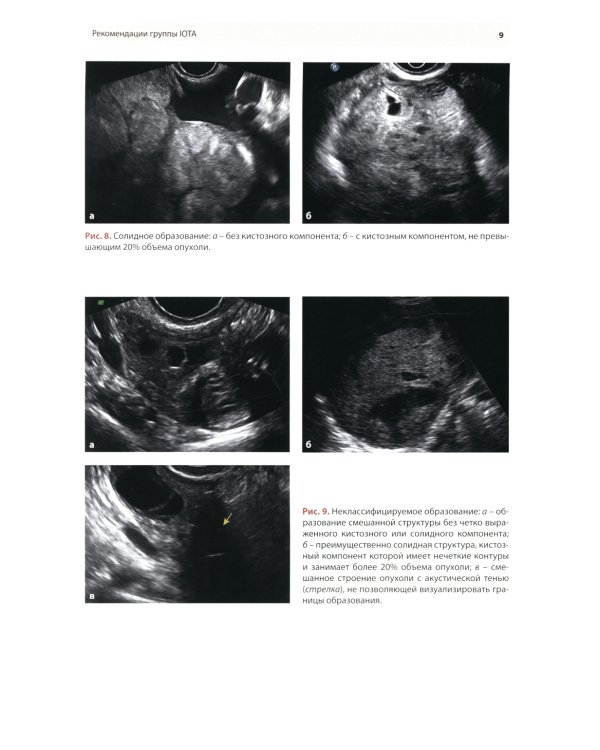

Методические рекомендации по стандартизации ультразвукового исследования с целью своевременной диагностики опухолевого процесса. Книга также включает вопросы дифференциальной диагностики физиологических изменений яичников, опухолевидных и опухолевых заболеваний и маршрутизации пациенток. Утверждено в качестве методических рекомендаций для проведения циклов первичной переподготовки врачей по ультразвуковой диагностике, тематического усовершенствования «Ультразвуковая диагностика в гинекологии», общего усовершенствования, ординаторов и аспирантов, проходящих обучение по направлению «Ультразвуковая диагностика, акушерство и гинекология».| Издательство | МЕДпресс-информ |